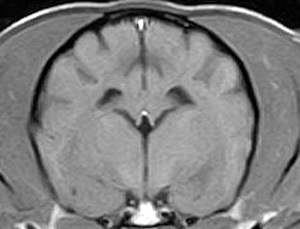

市内の先生からけいれん発作が出るとのことでMRI検査のご依頼がありました。検査では脳に構造上の異常を認めず、脳脊髄液検査も問題なく、特発性てんかんとの診断でご紹介もとの病院様での治療となりました。